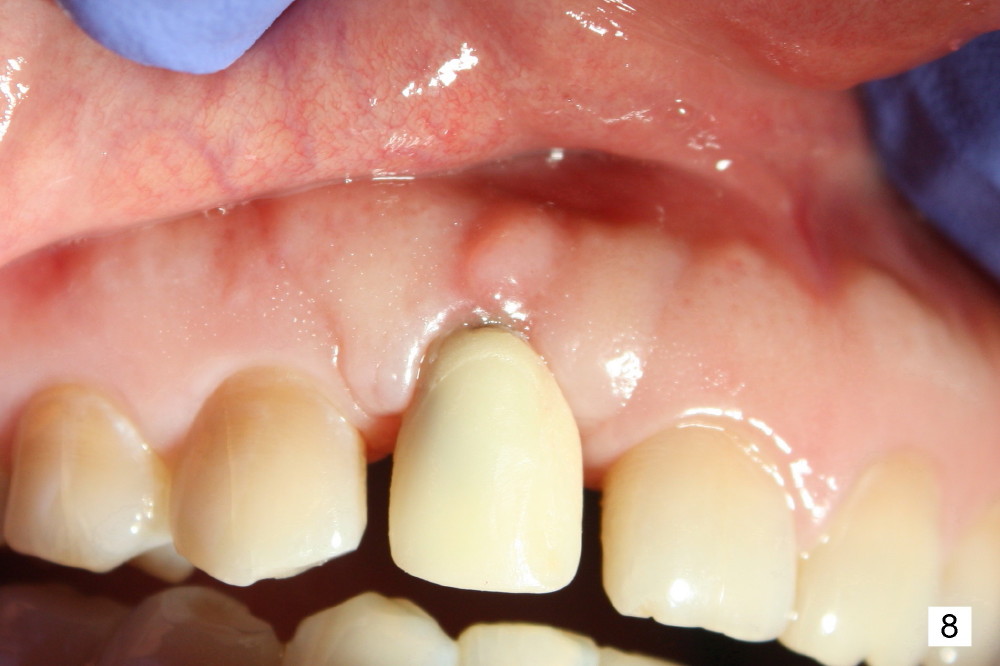

Fig.7,8 show the provisional 10 days and 1.5 months postop, respectively. When the provisional is removed, the implant/abutment is buccally malpostioned (Fig.9). It appears that segmental osteotomy is necessary. Fig.10 shows incision design. The implant and bone complex is to be moved to an ideal position (Fig.11,12). A block graft is inserted apically for internal fixation. An ortho wire is used for external fixation.